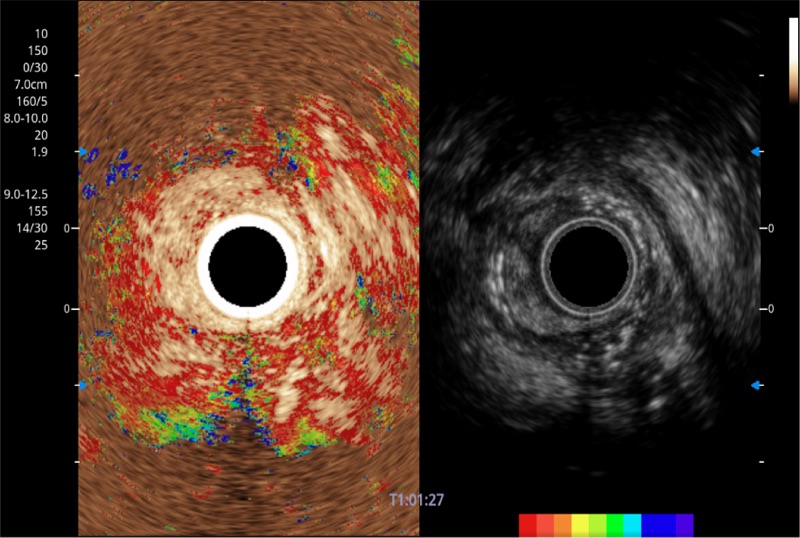

TIC时间强度分析曲线

具有四种造影成像效果

清晰显示胆总管及周围血管分布